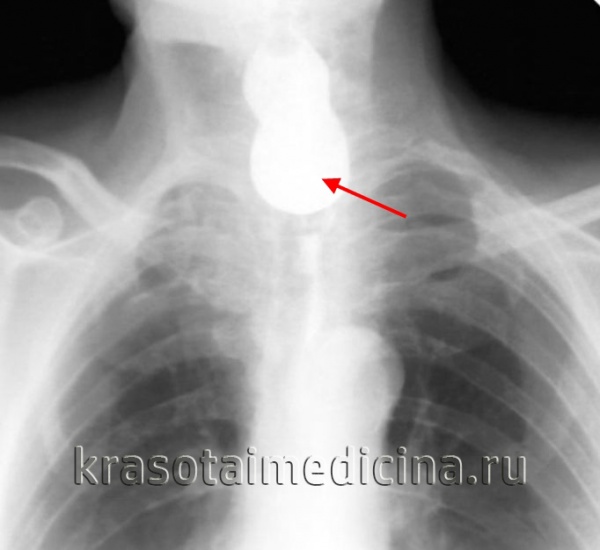

КТ: позади спавшегося пищевода выявляется дивертикул в виде заполненного воздухом образования.

(Справа) На аксиальной КТ без контрастного усиления у этого же пациента определяется дивертикул, заполненный дебрисом, жидкостью и пазом. Дивертикулы большого размера часто сдавливают пищевод, а в результате объемного воздействия смещаются в какую-либо одну сторону от средней линии.